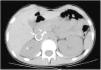

Niña de 13 años que consultó por astenia, hiporexia, sensación de mareo y dolor abdominal de dos meses de evolución. A la exploración destacaba hipertensión arterial (HTA) de 200/135 mmHg. La ecografía-Doppler mostró riñón derecho atrófico, con aneurisma de arteria renal derecha, confirmado con angio-TC (fig. 1) y arteriografía. Presentó como lesiones de órganos diana: daño renal agudo (creatinina máxima 1,45 mg/dL), retinopatía, miocardiopatía y microinfartos en sustancia blanca. Se descartaron aneurismas en otras localizaciones mediante angiorresonancia de cuerpo completo.

Se decidió tratar inicialmente mediante angioplastia y colocación de stent, no siendo posible por embolización espontánea. Dada la persistencia de HTA y práctica anulación funcional renal derecha, se decidió nefrectomía derecha (fig. 2), con mejoría progresiva de tensiones y función renal. Histopatología compatible con displasia fibromuscular (DFM). Tras dos años está normotensa, sin tratamiento y el filtrado glomerular estimado según la fórmula de Schwartz modificada es 66 mL/min/1,73 m2.